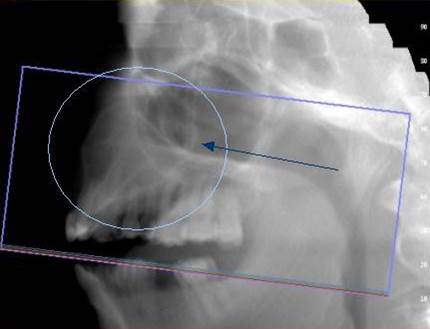

NewTom Giano

Jedná se o nejnovějším přístroj ze skupiny dentálních hybridních CBCT (3D) + 2D (pan i ceph) systémů. Opět umožňuje na základě jediného snímkování vytvořit všechny typy RTG zobrazení, které jsou pro lékaře potřebné. Používaná technologii tzv. „kuželového paprsku“ a speciální senzory pro minimální zátěž při snímkování pacienta.

Vyšetření pomocí tohoto přístroje (nebo 3D DVT - NewTom) a získaná data používáme pro každou implantaci, dále ve stomatochirurgii (zlomeniny čelistí, zuby moudrosti, cysty, onemocnění čelistního kloubu), ortodoncii (retinované zuby, nadpočetné zuby), parodontologii atd.